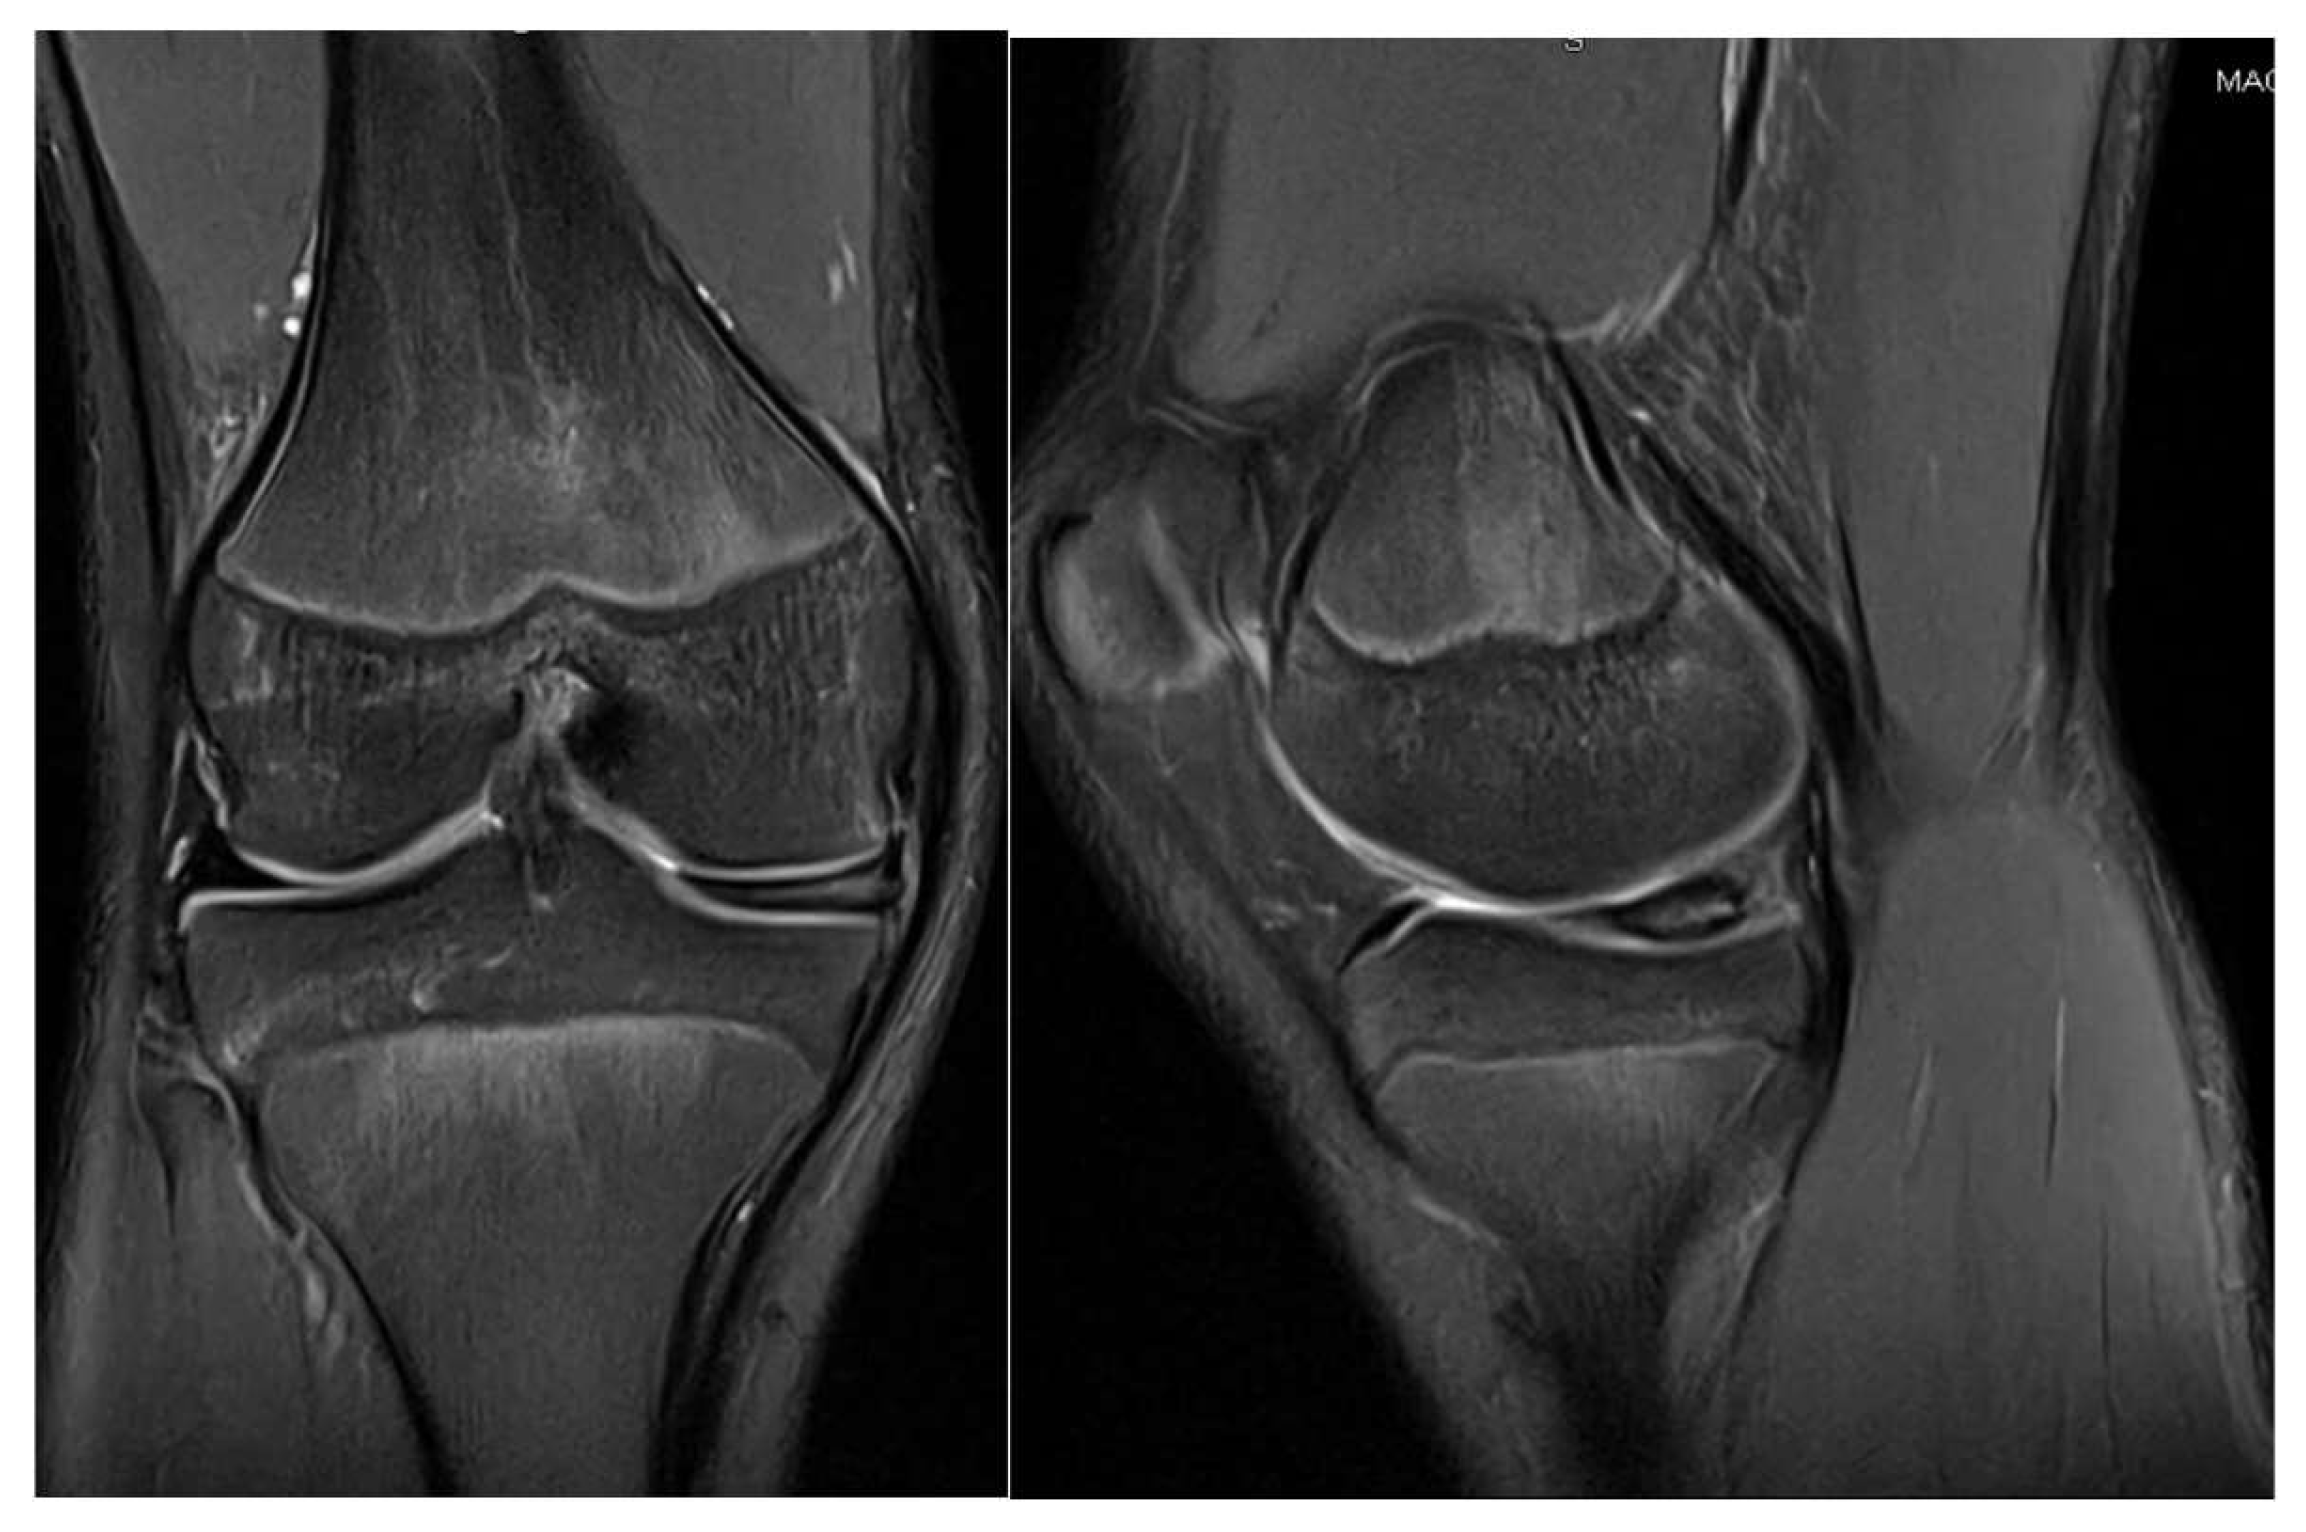

3.1. Case 1—P.E.

3.2. Case 2—S.C.S.

3.3. Case 3—G.L.